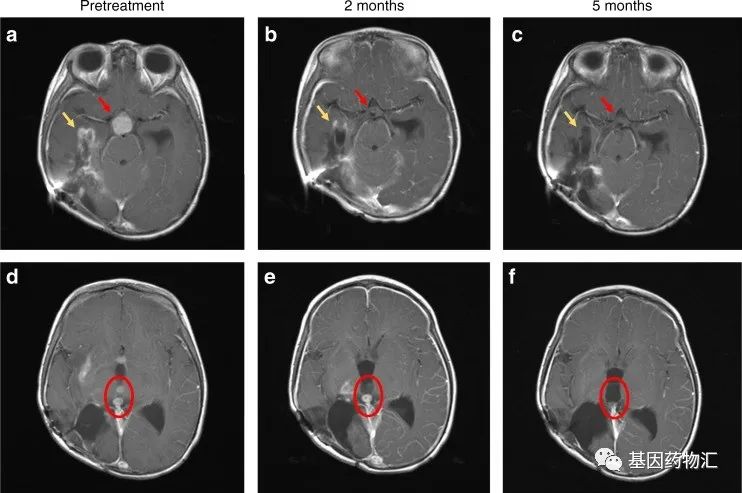

患儿5个月时被确诊患有脑瘤,最初出现呕吐和癫痫发作,MRI检测结果显示右侧脑室有一个6×3×2厘米的肿块。

幸运的是,拉罗替尼对这位患儿的治疗效果非常明显!仅4周,她不再出现嗜睡、头痛或呕吐,进食逐渐恢复,说话变得清晰;6周后,她能够独立思考,体力恢复,并且能够说出2~3个单次的句子;8周后,她能够跑步、跳舞,语言能力进一步地提高。

此时的MRI检测提示,她脑内的病灶都获得了改善或者缓解;5个月后,几乎所有的肿瘤都消退了!